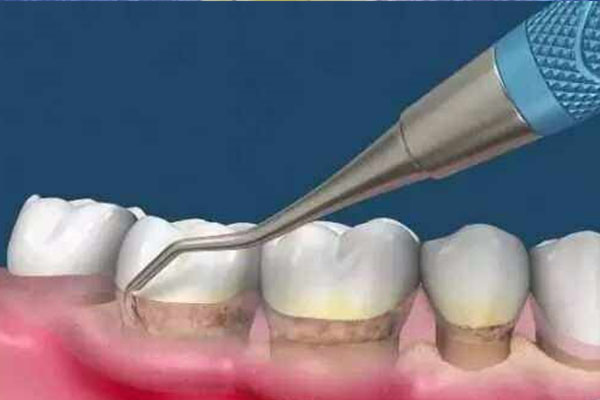

很多中老年患者发现,普通消炎药吃三天不见效,牙龈依然红肿出血,甚至发展到牙齿松动。这是因为传统药物渗透性差,难以深入牙周袋杀菌。【中老年口腔】采用纳米级消炎成分,配合缓释技术,药物能持续作用于患处72小时,48小时快速缓解急性炎症,同时修复受损牙龈组织。

建议优先选择局部用药,如消炎凝胶直接涂抹患处,配合含氯己定成分的漱口水。【中老年口腔】特别添加蜂胶提取物,既能增强牙龈免疫力,又避免长期使用抗生素导致的耐药性,更适合中老年人群体质。